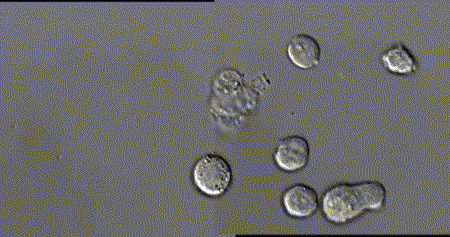

人体细胞总数在40~60万亿个之间,在这么多的细胞里,一些正常细胞由于物理、化学、病毒等致癌因子导致的原癌基因和抑癌基因突变后,就变成了癌细胞。一个正常人,每天会因各种原因产生6000个左右的癌细胞,而人体的免疫细胞则负责消灭癌细胞。美国细胞生物学会(ASCB)发布了一则微观大片,使用顶级的成像工具和技术,从免疫角度展示了人体中的一种免疫细胞T细胞杀死癌细胞的全过程。每个T细胞大约是人类头发直径的十分之一,它们在人体内不断巡逻,找出并杀死癌细胞或感染了危险病毒的细胞。当T细胞发现癌细胞时,通过分泌的毒素附着在癌细胞上,来检测、分辨正常细胞与癌细胞。查明之后,T细胞连接癌细胞,打破癌细胞外壁,向其表面引入毒性蛋白。一旦细胞毒素进入,癌细胞会逐渐衰弱、死亡。而T细胞继续在人体内巡逻,寻找下一个目标。其实除了上面提到的T细胞以外,身体里面还有很多免疫细胞在保护着我们,它们与癌细胞斗智斗勇,以抵御病毒保卫身体为终极目标。给大家分享几张免疫细胞“杀敌”的动图,来看看帅气的它们是如何英勇作战的:吞噬细胞在固有免疫中发挥重要作用,是清除致病微生物的重要免疫细胞。吞噬细胞包括两大类,即中性粒细胞(小吞噬细胞)及单核/巨噬细胞(大吞噬细胞)。两类吞噬细胞对入侵体内的微生物可极为快速的产生应答,尤以巨噬细胞的作用更为持久,是参与晚期固有免疫应答的主要效应细胞。NK细胞是T和B细胞并列的第三类淋巴细胞,不同于T、B细胞,它是具有直接杀伤靶细胞效应的一类淋巴细胞,靶细胞包括肿瘤细胞、病毒或细菌感染的细胞及机体某些正常细胞。NK细胞率先吹响战斗号角,以癌细胞头部为突破口发起进攻,癌细胞负隅顽抗NK细胞头部部队成功突破,大部队快速抵达战场,癌细胞瞬间瓦解NK细胞具有抗肿瘤、抗感染、免疫调节等功能,在病毒和寄生虫的抗感染免疫早期发挥重要作用。B细胞是体内产生抗体(免疫球蛋白)的细胞,B细胞也存在不同的亚群,主要执行体液免疫,也具有抗原提呈功能。通常情况下,人体的免疫系统可以高效地识别和消灭癌细胞,保证我们的身体健康。这些人体的天然“健康卫士”,绝对不会放过每一个逃逸的癌细胞。即便癌细胞成功逃逸进入血液,免疫细胞也会对癌细胞发起猛烈进攻。免疫细胞可穿过血管壁奔赴“战场”,向炎症和创伤组织进军、围剿。随着人类生命科学的不断发展,科学家们揭示了免疫细胞杀死癌细胞的作用机制,并证实了免疫细胞在对抗癌症上具有无可比拟的先天优势,根据这一特性,人类科学家探索出一系列通过补充T细胞、NK细胞、甚至使用CAR-T、CAR-NK等“大杀器”,来对抗癌症的免疫疗法。厉害了!我的免疫细胞!与病菌抗争的场面简直可以拍成一部精彩的战争电影了!想象一下,如果身体缺少它们每天顽强地抗敌的话,我们会怎样呢?应该连最基本的呼吸都难以做到了吧,毕竟空气中有那么多细菌,少了免疫细胞我们真没办法存活了......但是还是想跟大家说的一个真相是,免疫细胞虽然很强大,但是它们也会随着身体的老化而变得衰弱甚至死亡。因为少了免疫细胞的保护,身体对外来病毒的抵抗力就会变弱,人就会很容易生病。 |